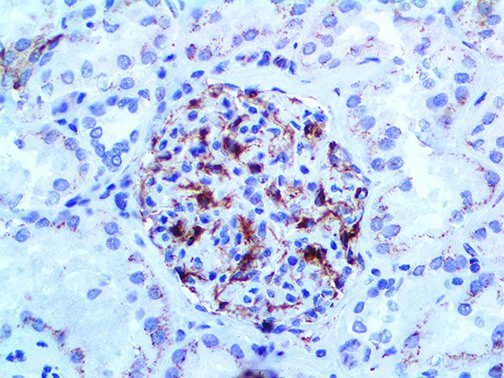

It is the ICU physician who is most likely to witness one of the deadliest manifestations of the abnormal immunological response, the cytokine storm syndrome (CSS). This response is also referred to by some as the cytokine release syndrome (CRS). CSS is characterized by continuous activation and expansion of macrophage and lymphocyte populations, which secrete large amounts of cytokines, causing the cytokine storm. This massive cytokine release is akin to hemophagocytic lymphohistiocytosis (HLH) disease, a syndrome characterized by initial unchecked and persistent activation of cytotoxic T lymphocytes and NK cells.

Clinical and laboratory manifestations of HLH include fever, enlarged liver and/or spleen, neurologic dysfunction, coagulopathy, liver dysfunction, cytopenias (i.e., low levels of erythrocytes, leukocytes, and/or platelets), hypertriglyceridemia, hyperferritinemia, hemophagocytosis, and eventually diminished NK cell activity as the immune system becomes progressively paralyzed. HLH can be familial (primary HLH) or secondary to another disease process (sHLH), such as rheumatic disease, in which it is referred to as macrophage activation syndrome (MAS, characterized by elevated ferritin).